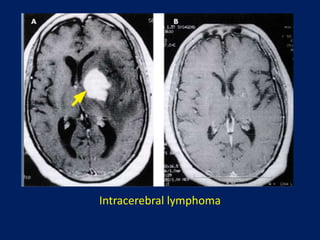

Intracerebral lymphoma